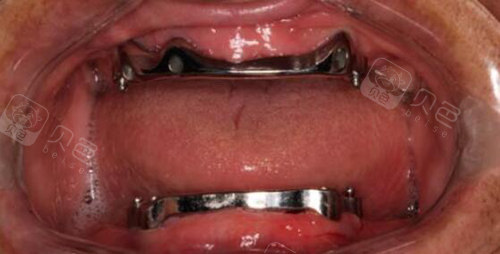

奥齿泰系统两例下颌杆卡覆盖义齿

图片尺寸510x340